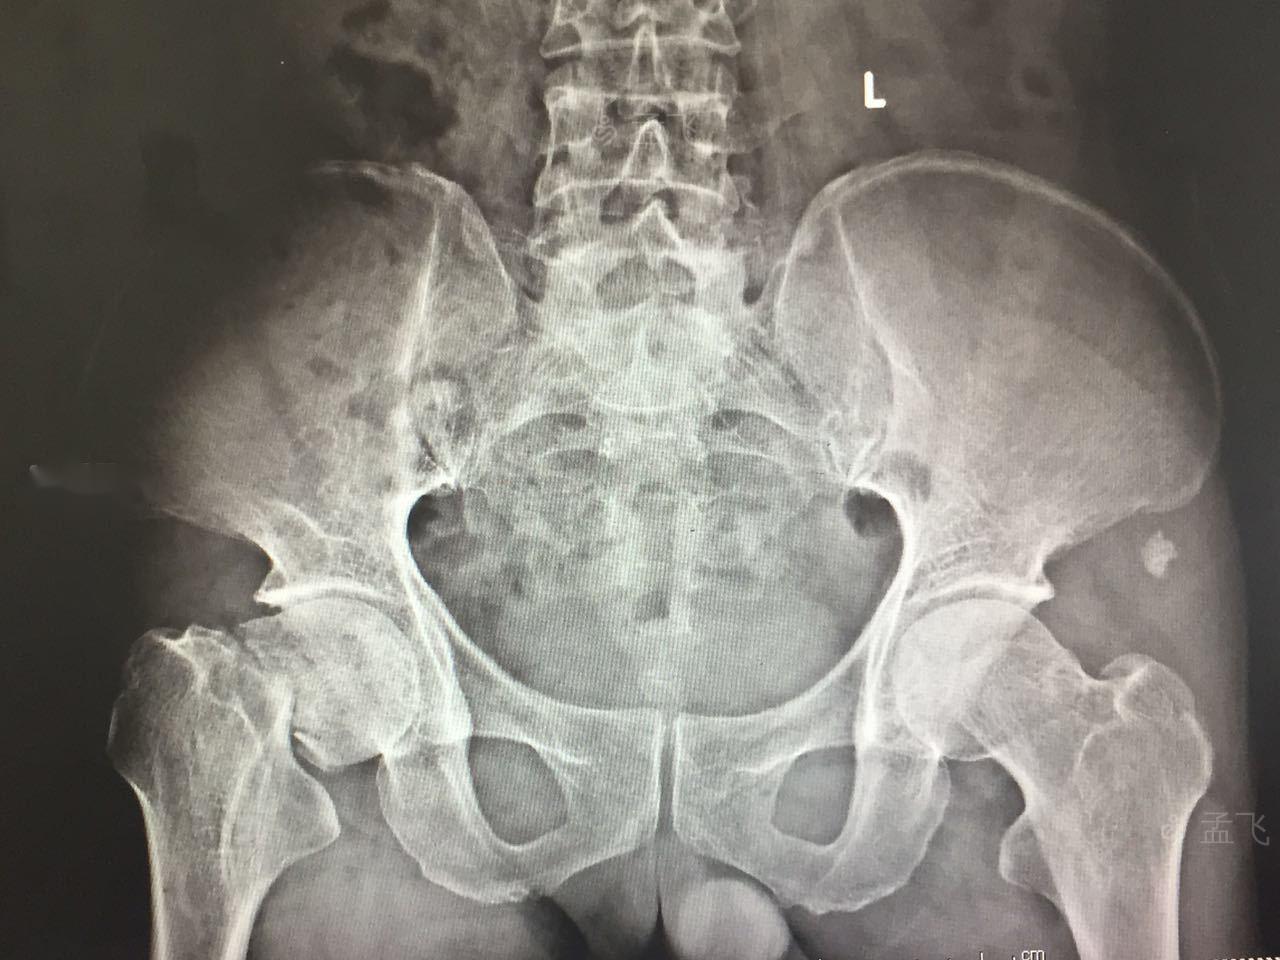

右股骨颈骨折术前